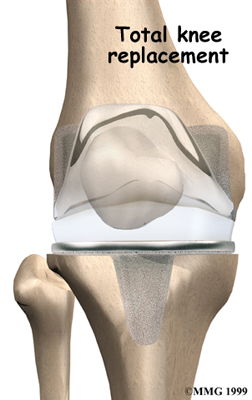

Artificial Knee Replacement

An artificial knee replacement is the ultimate solution for advanced knee OA.

Surgeons prefer not to put a new knee joint in patients younger than 60. This is because younger patients are generally more active and might put too much stress on the joint, causing it to loosen or even crack. A revision surgery to replace a damaged prosthesis is harder to do, has more possible complications, and is usually less successful than a first-time joint replacement surgery.

Related Document: FYZICAL Rockledge's Guide to Artificial Joint Replacement of the Knee